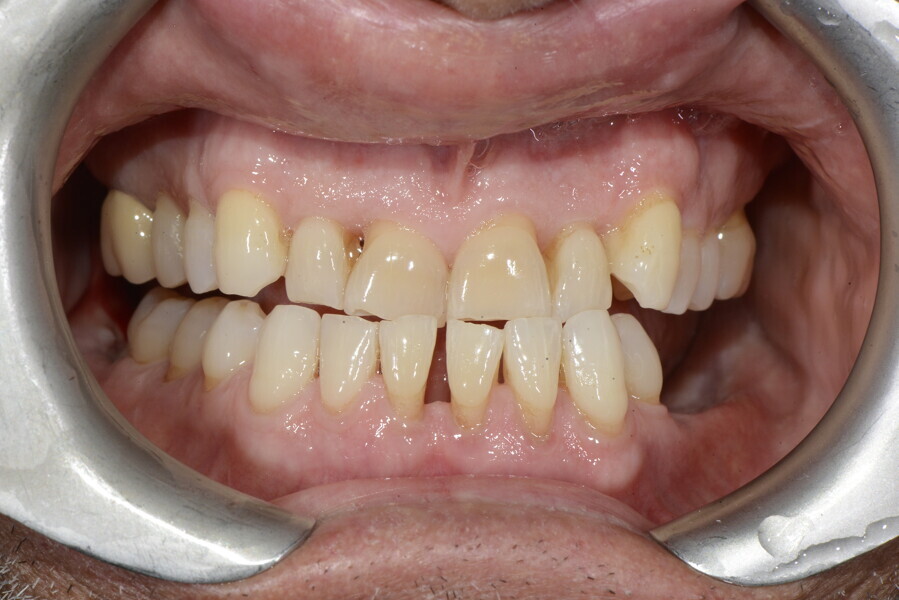

The 58-year-old patient wished to improve his oral aesthetics and function, complaining of mobility of the posterior teeth and wear of the anterior teeth. After data collection, a very complex situation was identified (Figs. 11–13):

1. severe periodontitis with poor prognosis of some teeth;

2. anterior crossbite;

3. severe wear mainly of the anterior teeth and compensatory eruption;38

4. atypical swallowing and lower posture of the tongue at rest;

5. masticatory dysfunction during the mastication test; and

6. no significant signs of temporomandibular disorder.

This patient, like all patients requiring interdisciplinary rehabilitation, had to first undergo periodontal treatment and caries restoration (Fig. 17). At the same time, it was important to rehabilitate swallowing with Froggymouth and relax the masticatory muscles and relieve the TMJs with an occlusal device. We could then study the orthodontic treatment plan using Invisalign ClinCheck (Align Technology) and showed the treatment plan to the interdisciplinary team and to the patient (Fig. 18). We were then able to create the correct sequence of orthodontic treatment, bone augmentation and implant surgery needed for the posterior edentulous spaces.